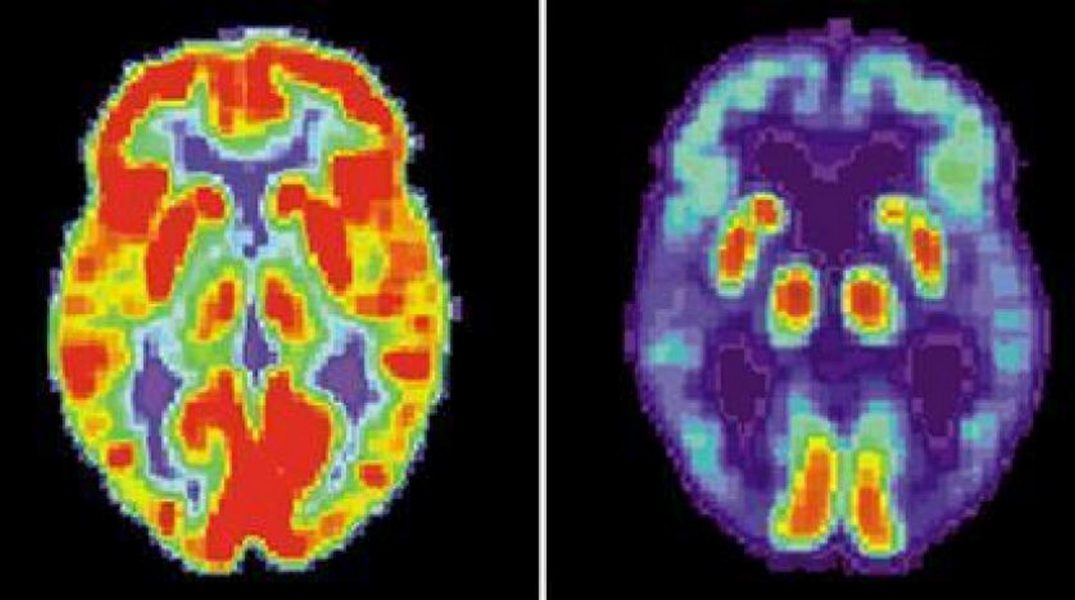

قام أطباء الأعصاب في الصين بتشخيص إصابة شاب يبلغ من العمر 19 عاماً بمرض «ألزهايمر»، ما يجعله أصغر شخص يتم تشخيصه بهذا المرض في العالم، وفقاً لموقع «ساينس أليرت».

وبحسب الموقع، بدأ الشاب يعاني من تدهور الذاكرة في سن 17 عاماً، وتفاقمت الخسارة المعرفية مع مرور السنين.

ومع ذلك، لم يتمكن الباحثون في جامعة العاصمة الطبية في بكين من العثور على أي من الطفرات المعتادة المسؤولة عن البداية المبكرة لفقدان الذاكرة لدى الشاب الذي تم تشخيصه، ولا أي جينات مشتبه بها عندما أجروا بحثاً على مستوى الجينوم.

بعد عام من إحالته إلى عيادة الذاكرة، أظهر تراجعاً في الاستدعاء الفوري، وكانت درجة الذاكرة الكاملة للمريض أقل بنسبة 82 في المائة من نظرائه في سنه، في حين أن درجة ذاكرته الفورية كانت أقل بنسبة 87 في المائة.

هناك حاجة إلى متابعة طويلة الأمد لدعم تشخيص الشاب، لكن فريقه الطبي يقول إن المريض «يغير فهمنا للعمر النموذجي لظهور مرض ألزهايمر».

وكتب طبيب الأعصاب جيانبينج جيا وزملاؤه: «كان المريض مصاباً بمرض ألزهايمر مبكراً جداً مع عدم وجود طفرات ممرضة واضحة»، ما يشير إلى أنه لا يزال من الضروري استكشاف أسبابه المرضية.

تُظهر دراسة الحالة أن مرض «ألزهايمر» لا يتبع مساراً واحداً، وهو أكثر تعقيداً مما كنا نظن، حيث يظهر عبر العديد من الطرق ذات التأثيرات المتفاوتة.